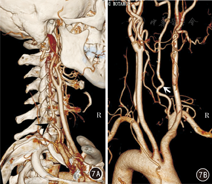

VA的变异包括管径发育细小(图1,图2,图3)、起源部位变异(图2、图4)、各节段行程变异(图2,图3,图4,图5,图6,图7)、数目变异(图4)、分支和异常吻合变异(图5)等。单一变异以一侧VA发育细小或狭窄形成两侧VA不对称最为多见,有66例(33.0%),其中右侧VA细小形成的左侧优势型VA 42例(右VA管径小于3 mm者31例),左侧VA细小形成的右侧优势型VA 24例(左VA管径小于3 mm者19例)。19例MCV中,有12例系由双侧细小的VA(图1)或一侧细小VA合并其他类型变异形成(图2、图3)。

本组有28例(14.0%)30条VA共34个部位表现为不同节段的多种行程变异,如双侧VA分别经不同水平的颈椎横突孔上行入颅(图2、图4、图7);或出C2横突孔后未经过C1横突孔,直接经C1和C2后侧椎弓间进入椎管,形成所谓"C2节段性VA"(图5、图6);或行程中出现折曲向下位椎体内疝入形成椎体动脉环(图6);或出C1横突孔后向C1侧块嵌入,经完整或不完整的骨桥内入颅(图3)等。其中15例(7.5%)行程变异合并其他类型和部位的变异表现为MCV,其中6例(3.0%)同时存在2个部位的行程变异(表2),是最常见的MCV组成类型。

VA起源变异是指VA一侧或双侧起自除同侧锁骨下动脉以外的动脉分支,较常见的是直接起自主动脉,同时多伴有行程的变异(图2、图4)。本组有5例(2.5%,5/200)左侧VA起自主动脉弓,均伴行程变异等表现为MCV。见表2。

尽管诊断VA血管病变以细小血管分支显示清楚的DSA为金标准[1,2,9],但DSA常规采用减影成像,对VA行程变异、下位颈椎椎体环、C2节段性VA、C1骨桥等多种变异进行观察时,由于骨结构被减影而易导致漏诊。相反CTA对上述多种情况的观察有其优势,可利用多种后处理影像技术,观测VA的解剖结构与变异,观察其行程中与各骨结构的关系[1,2,3,4,5,6,7,8,9,10]。需要指出的是,部分影像科医生在分析头颈部CTA影像时,仅简单分析减影后的纯血管VR影像,发现血管管径、数目、起源等变异和病变,由于没有椎骨结构作参照,漏诊大量的VA行程变异和MCV;要注意采用多种图像后处理技术,认真分析原始横断面影像和带椎骨的VR影像,观察VA的行程,充分发挥CTA的优势,全面发现各种VA变异和病变。